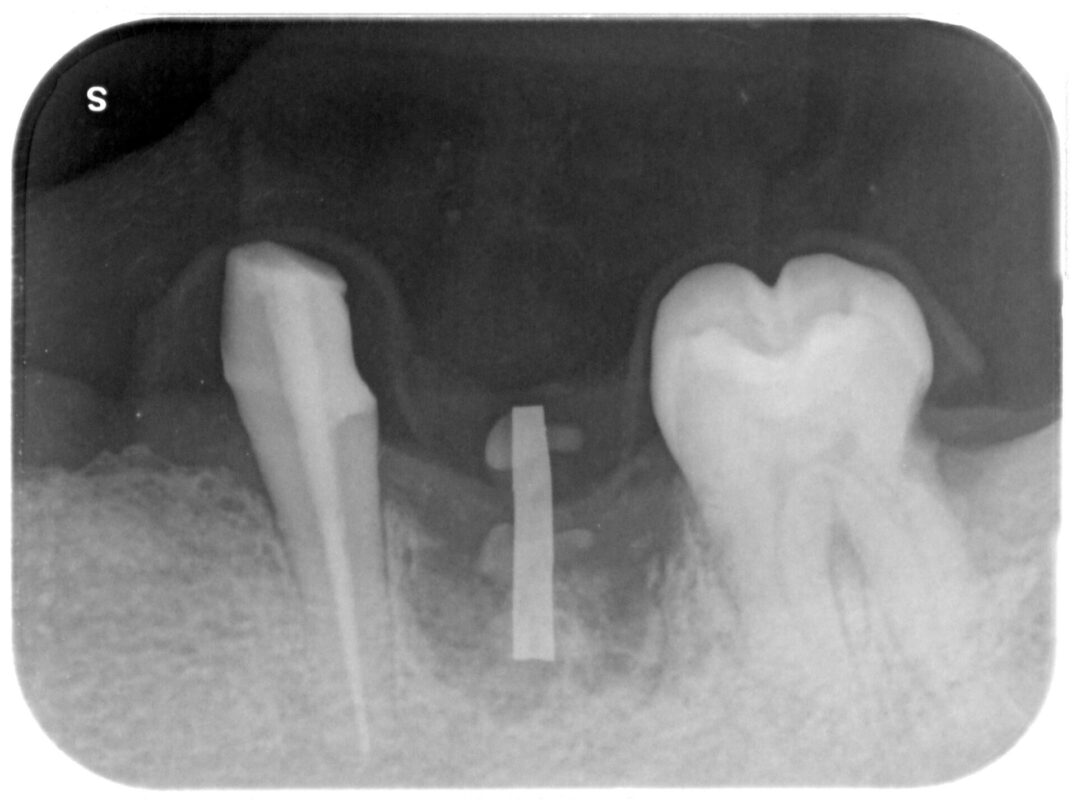

術前写真

アナログステントで位置決めをします

抜歯後2ヶ月